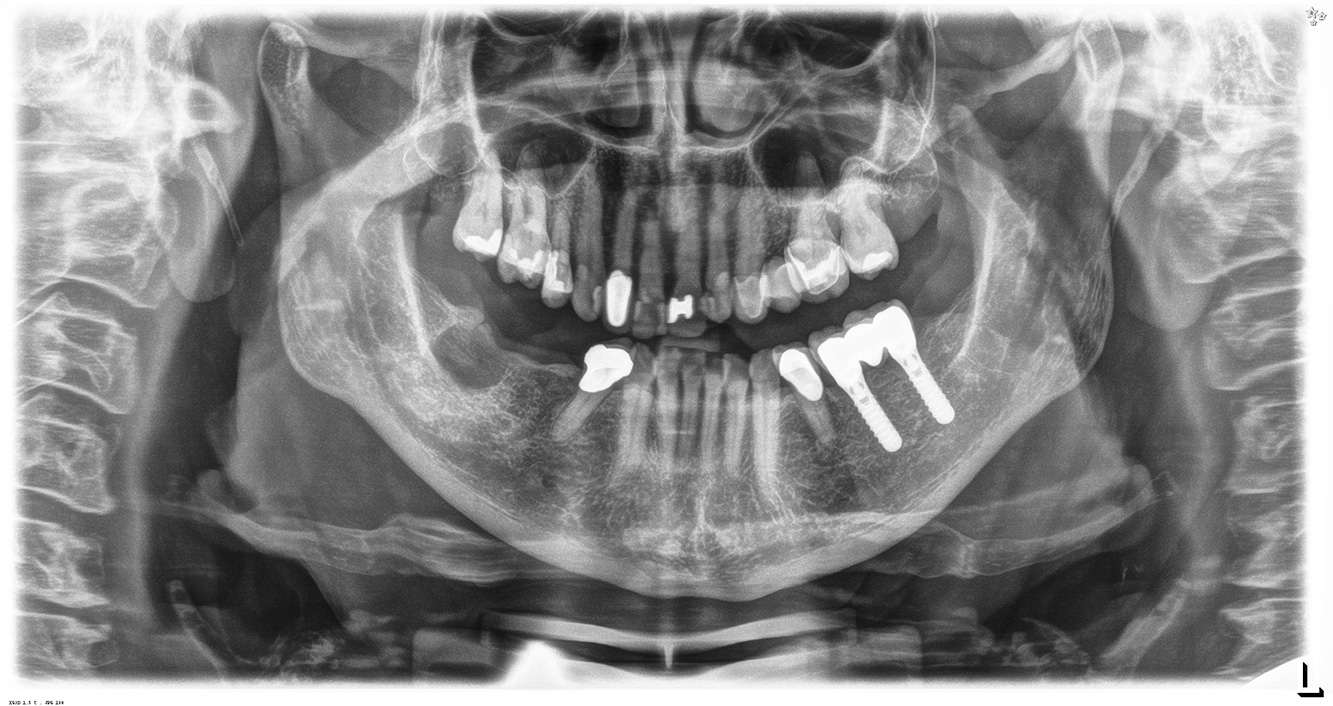

In the medical history, the 55-year-old patient states that he has no systemic disease and is not taking any medication. The patient’s lifestyle is similarly unremarkable. The patient has a few tooth restorations and two implants (2nd and 4th quadrants). On the basis of current findings, gingivitis is identified in an otherwise stable periodontal condition on the reduced periodontium (stage III, grade A). more

The healthy patient with pre-existing periodontal disease & peri-implantitis